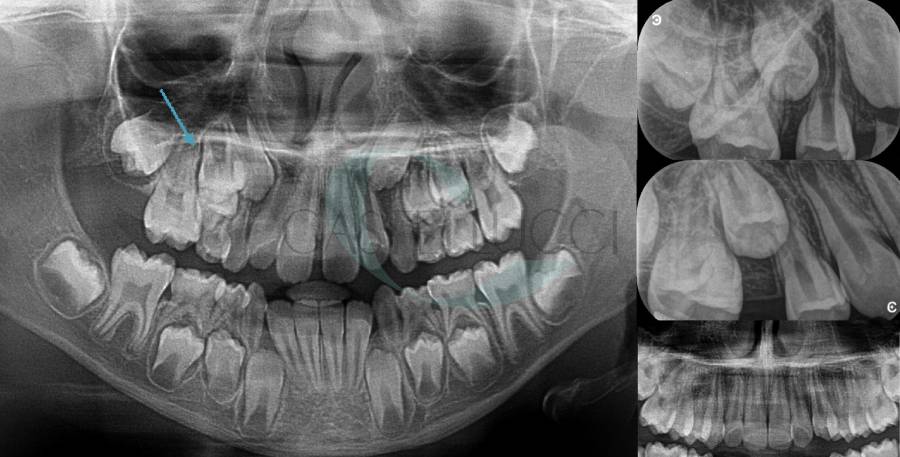

• Disinclusione chirurgica degli elementi dentari permanenti ritenuti